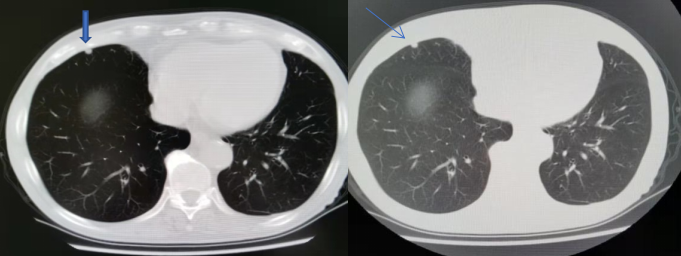

随诊:2020年7月17日胸部CT(图1)右中肺新发小结节,考虑转移。

图1.2020年随诊胸部CT

随诊:2021年1月3日胸部CT:右中肺结节增大,考虑转移。

图2. 2021年随诊胸部CT